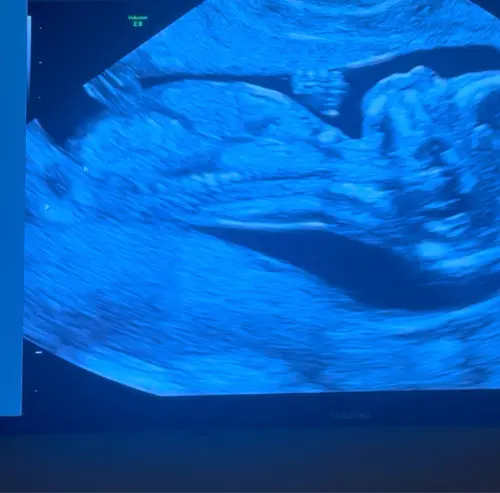

13 weken. Wat denken jullie?

Beentje zit ervoor

De nub is hier goed te zien. Denk boy maar ben niet zeker vanwege lighoudin ...

Dank voor je reactie! Het is een video opname, hier nog een paar screenshots.